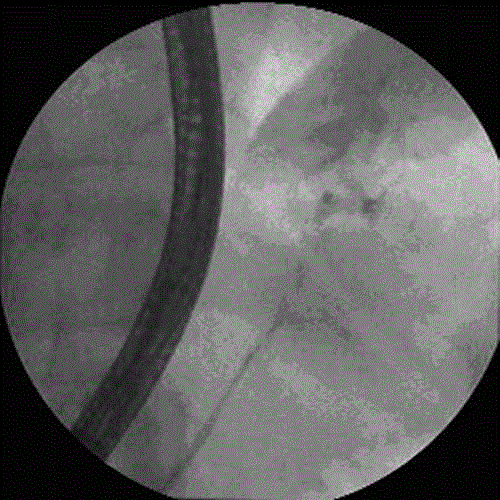

Figure 3. Pancreatogram demonstrating the normal size of a pancreatic duct from head to tail. There is a significant extravasation of contrast from the tail into a large cyst (white arrow).